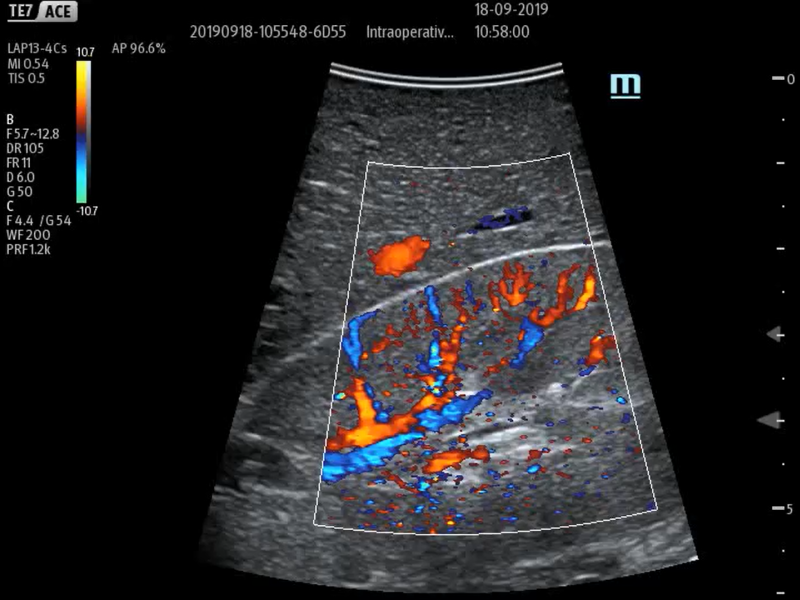

With its superior image quality, simple touchscreen operation and class-leading intelligent tools, the Mindray TE7 ACE is designed to simplify and speed-up ultrasound examinations.

Images